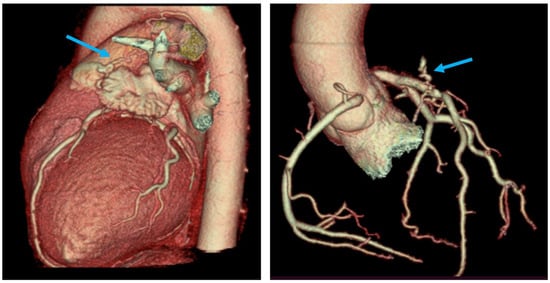

Figure 4. Coronary CT angiography (CTA)—three-dimensional volume-rendering images vividly depict the presence of a fistulous connection between the proximal segment of the LAD and the pulmonary trunk (marked with the blue arrow). Coronary arteries present anatomic origins of the right and left sinuses of Valsalva and coronary co-dominance. No significant coronary artery stenoses were visualized.